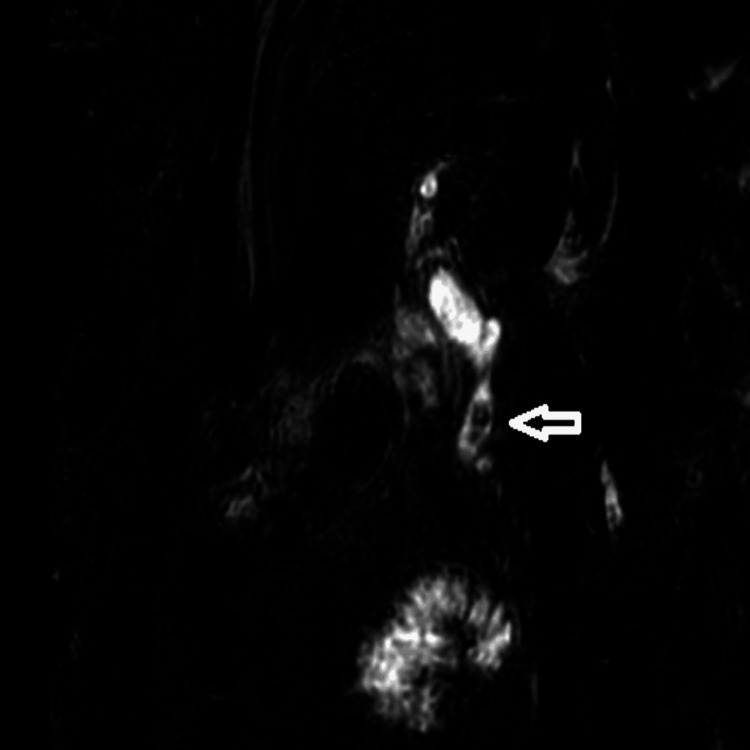

Following the surgery, the patient continued to have a persistent pain in the abdomen and developed jaundice over the next few days. A follow-up magnetic resonance cholangiopancreatography (MRCP) showed an enlarged common bile duct with several stones, as observed in Figure 1. It was decided that this would be treated using endoscopic retrograde cholangiopancreatography.